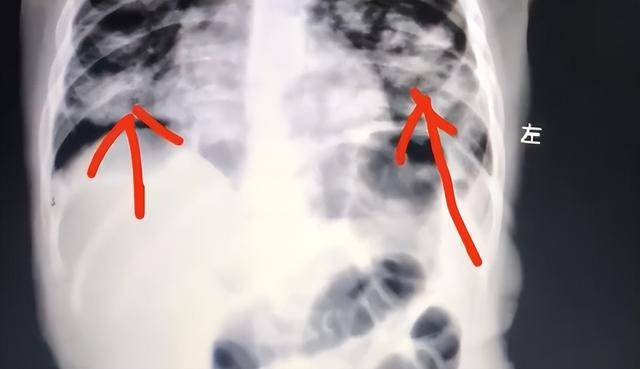

快科技12月25日消息,大象新闻报道,近日,河南南阳一名一岁宝宝在家中误服了用于皮肤护理的紫草油世界杯皇冠信用平台。

家长发现后,第一反应是立即用手抠孩子喉咙催吐,不料这一做法反而导致油脂被吸入肺部,引发严重吸入性肺炎世界杯皇冠信用平台。目前,孩子肺部已出现大面积感染变白。

据了解,这瓶紫草油原本是家长为孩子涂抹臀部所用世界杯皇冠信用平台。事发时,宝宝不慎误饮一口,母亲情急之下采取催吐措施,却刺激孩子剧烈咳嗽,致使部分油脂被吸入气道,进入肺部。

油脂类物质一旦进入肺部,难以自行排出,会迅速引发炎症和感染,情况十分危险世界杯皇冠信用平台。